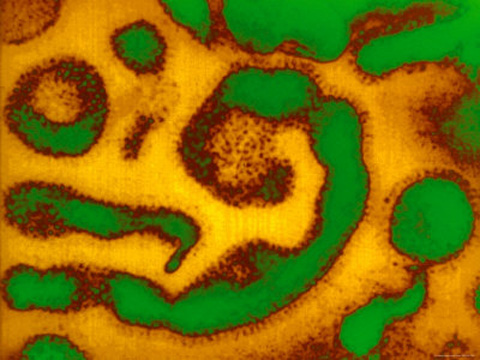

(“Symptoms of the Common Cold Syndrome are Caused by over Two Hundred Different Viruses.” Photographer not indicated. Right-clicked from www.allposters.com, used here for non- commercial purposes, under the terms of , free service by blog-use of image provided by said site.)